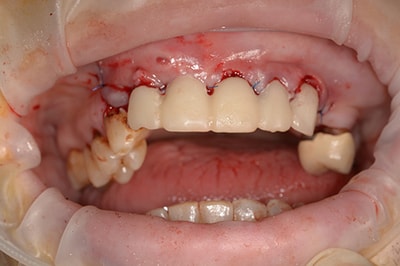

Cas numero 2 :

Etude du cas et proposition

Cas terminé